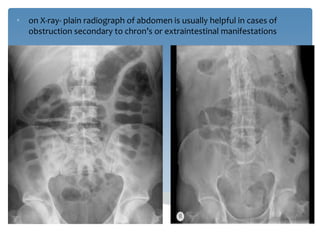

Crohns Disease Xray

Crohn's disease | Radiology Case | Radiopaedia.org Crohn's Disease Radiology: CT, MRI, Ultrasound, and More LearningRadiology - Crohn Disease, Regional Enteritis Crohn disease - X-ray: MedlinePlus Medical Encyclopedia Image | Crohns Disease Xray